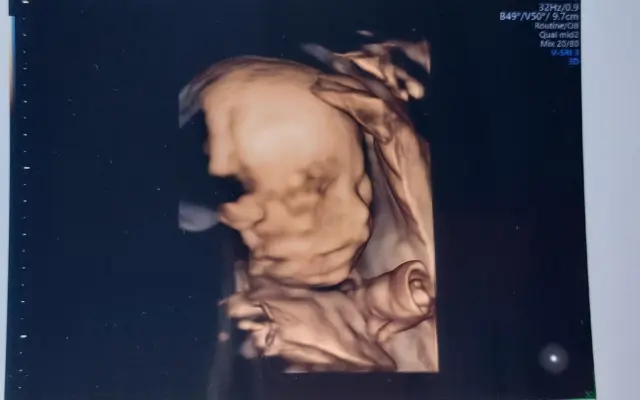

Fotogalerie